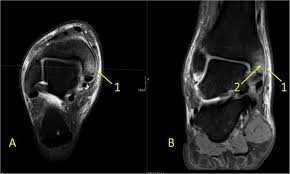

Figure 2 From Medial Impingement Of The Ankle In Athletes Semantic Scholar

Figure 2 From Medial Impingement Of The Ankle In Athletes Semantic Scholar from d3i71xaburhd42.cloudfront.net

Explore the five types of breaks and when surgery may be required by your doctor. Bone spurs are abnormal spiking outgrowth of the bone around the edge or border of the bone. Knowledge of this is useful for massage therapists and other clinical professionals. Case contributed by dr henry knipe ◉ ◈. If talar rotation continues, the medial malleolus is avulsed and the deltoid ligament may rupture. Marked soft tissue swelling over the lateral malleolus with a small bony fragment and increased lucency at the tip which. Spurs may be observed over shaft or end of the bone involved in joint formation. What are treatment options for a bone spur?